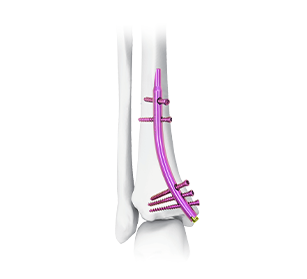

Distal Tibial Nail Visualization

Distal Tibial Intramedullary Nail

The Distal Tibial Intramedullary Nail (DTN) is indicated for a variety of tibial conditions, including simple, spiral, comminuted, long oblique, and segmental shaft fractures (particularly of the distal tibia), as well as distal tibial metaphyseal fractures, non-/mal-unions; it may also be employed, often with specialized devices, for managing bone defects or limb length discrepancies (such as lengthening or shortening).

Surgical Procedure Visualization - Distal Tibial Nailing Technique